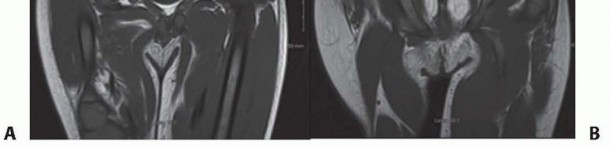

Illustration 3 for Treatment for Congenital Femoral Deficiency: What You Need to Know Illustration 4 for Treatment for Congenital Femoral Deficiency: What You Need to Know Illustration 5 for Treatment for Congenital Femoral Deficiency: What You Need to Know Illustration 6 for Treatment for Congenital Femoral Deficiency: What You Need to Know FIG 2 • A. Paley type 1b CFD (subtrochanteric type) shown by illustration, radiograph, and MRI. Note the nonossified subtrochanteric cartilage B. Paley type 1b CFD (neck type) shown by illustration, radiograph, and MRI. Note the nonossified neck. *

Other imaging studies that are useful include magnetic resonance imaging (MRI) and arthrography of the hips. All Paley types 1b and 2 should have an MRI after age 18 months to confirm whether there is a cartilaginous connection between the femoral head and shaft (

FIG 4 *).

in the proximal femur, and the CFD is classified as type 1b. The arthrogram is also useful to differentiate between Paley types 2a and 2b. Both 2a and 2b might have a femoral head present; the difference is whether the femoral head is fused to the acetabulum or not. If dye can be injected into a joint space, the hip can usually be classified as type 2a. In some cases of type 2a, the dye can be seen to outline a cleft through the femoral neck. Illustration 8 for Treatment for Congenital Femoral Deficiency: What You Need to Know Illustration 9 for Treatment for Congenital Femoral Deficiency: What You Need to Know FIG 4 • MRIs of Paley type 2 CFD. The femoral head is clearly seen (A), and in a separate cut, one sees the proximal femur in a different plane (B). *